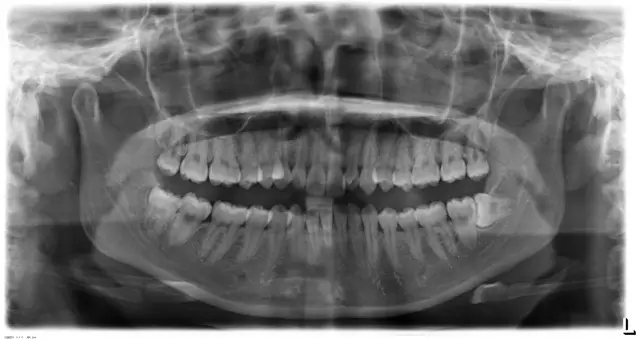

Damon 病例分享:安氏 II 類二分類露齦笑的矯治(董一磊)

患者信息